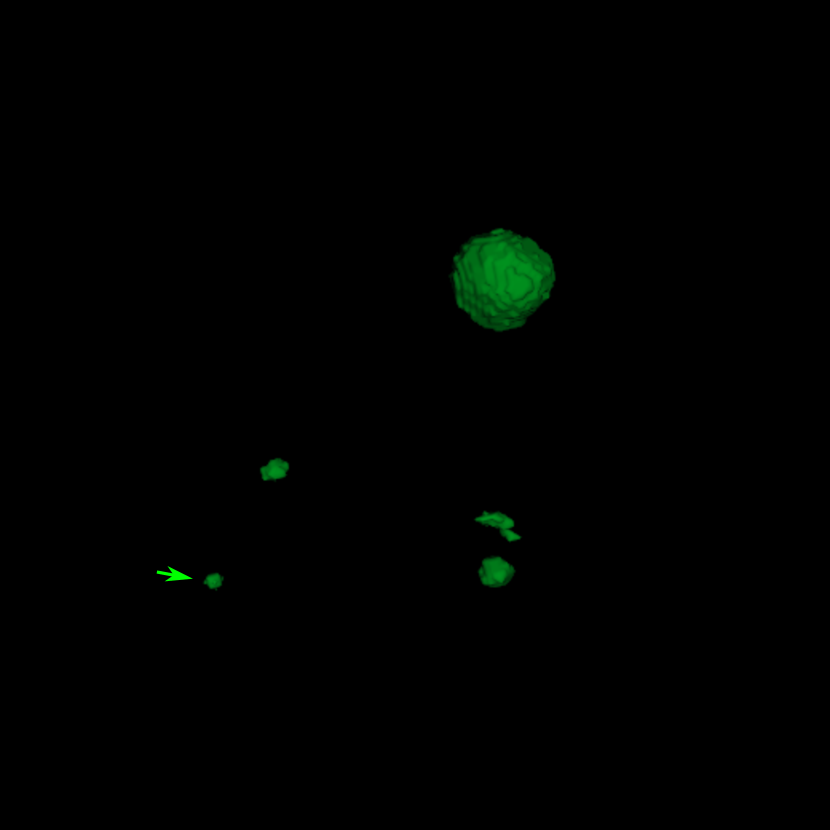

Figure 4: Three examples of FN metastases by baselinesubscriptbaseline\mathcal{M}_{\text{baseline}} (the baseline DeepMedic model trained with BCE loss), which are detected by DeepMedic with the JVSS (α=0.995𝛼0.995\alpha=0.995) loss. The segmentation masks are indicated by green color. Two zoomed-in ROIs without and with the segmentation mask are displayed on the left and right top corners respectively for each patient.

The metastasis-level evaluation of DeepMedic and DeepMedic+ models trained with different loss functions is displayed in Tab. 1. The baseline DeepMedic model achieves a sensitivity of 0.853 (237/278) and a precision of 0.691 (237/(237 + 106)). In other words, among the 278 metastases, 237 TP metastases are detected, while 106 FP metastases are also marked. The FN metastases are mainly tiny metastases, as displayed in the top left regions-of-interest (ROIs) of Fig. 4 where three exemplary FN metastases are displayed.

With the JVSS loss, depending on the value of α𝛼\alpha in Eqn. (4), the sensitivity and precision can be adjusted. When α=1𝛼1\alpha=1 where high sensitivity is desired, DeepMedic achieves a high sensitivity of 0.975 (271/278) but a low precision of 0.275 (271/(271 + 718)). Among all the 278 metastases, 271 are successfully detected, but 718 FP metastases are detected. With a slight smaller α𝛼\alpha value, i.e., α=0.995𝛼0.995\alpha=0.995, a high sensitivity of 0.946 (263/278) is achieved, while the precision is increased to 0.516 (263/(263 + 247)). The number of FP metastases is decreased from 718 to 247. In the top right ROIs of Fig. 4, the metastasis positions of the three exemplary images are correctly detected by DeepMedic trained with the JVSS loss (α=0.995𝛼0.995\alpha=0.995).

In Fig. 4, the volume sizes of the three metastases are all smaller than 0.1 cm3. Therefore, it is very challenging for DeepMedic, and for human experts as well, to identify them, especially with many vascular structures being similar to them. These small metastases consist of very few voxels and there is ambiguity due to partial volume effects in the periphery of the metastases. For such tiny metastases, DeepMedic only detects a few voxels, or even one voxel only, in each metastasis region. For example, in Fig. 4, not all the metastasis voxels are covered by the segmentation mask. Nevertheless, detecting their existence already has important clinical value. In general the segmentation accuracy of DeepMedic does not change or changes slightly for all other large metastases. This is demonstrated by the mDSC values in Tab. 1 and the 3D rendering in Fig. 9. Interestingly, mDSC is even improved using the proposed JVSS loss in senssubscriptsens\mathcal{M}_{\text{sens}} as compared to BCE alone, which illustrates that the introduction of the proposed VSS loss does not compromise the accuracy of individual segmentation masks in detected metastases.